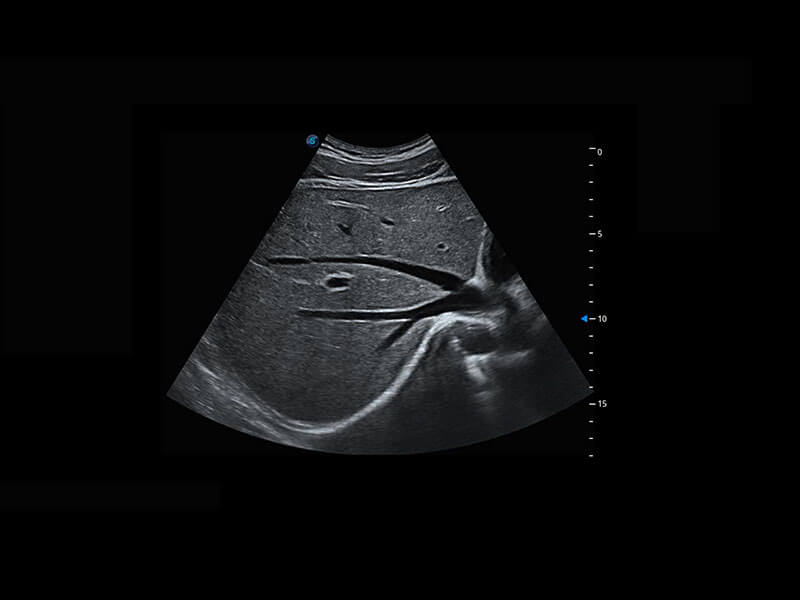

中晚孕筛查

P60提供简单易学易用的高端诊断工具,为您中晚孕筛查提供快速清晰的解剖信息。

1 OFD(HC): 87.03 mm

HC: 251.00 mm

GA: 27w 1d

HC/AC: 96.13 %

2 BPD: 70.56 mm

GA: 28 w 2d

S-Fetus(acq.)

& S-Fetus(meas.)

S-Fetus

S-Fetus能够助您在实时扫查过程中自动识别标准切面、自动测量并录入报告。一个按键,即可快速、高效地获取胎儿生理指标,简化您的产科检查操作。